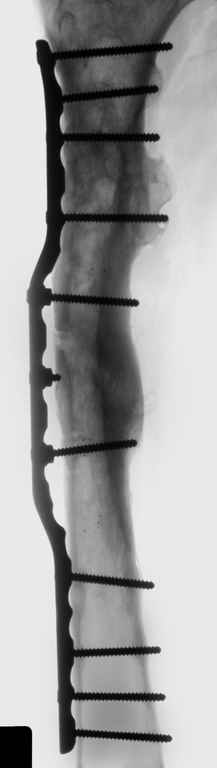

Можно применить гвоздь с множественными косыми остеотомиями, но я посчитал, при применении 4.5 мм длинной пластины или L-образную пластину с короткой ножкой в шейку, шанс на удержание отломков более вероятная, чем гвоздем.

Двойную остеотомию при лечении можно делать так: латеральным субвастус доступом (с приподниманием вастус латералис) обнажается латеральная поверхность бедра, заранее сделанным преоперационнным планом определяется место остеотомии, периостиум обнажается только по этому

плану, т.е. по линии остеотомии. Перед остеотомией накладывается дистракционный аппарат, делается остеотомия и медленная дистракция, накладывается по длине пластина, дистракция и компрессия по

необходимости, фиксируются проксимальный и дистальный концы пластины 4.5 мм шурупами, косо для стабильности, затем работа с медиальным

фрагментом.

Необходимо создание медиальной компрессии, которая создастся с помощью коротких шурупов против латерального кортекса. Чтобы эти шурупы не выпали из дырок на пластине, надо применить резьбовую шайбу Schulle nut, который имеет резьбу точно подходящую к резьбе шурупа, и ставится с внутренной стороны пластины, те конструкцию locking plate.